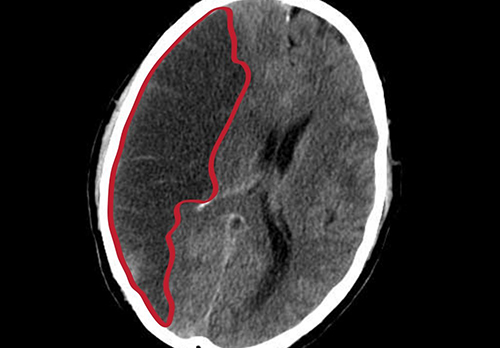

Ученые с помощью МРТ обнаружили, что накопление железа во внешнем слое мозга связано с ухудшением когнитивных функций у людей с болезнью Альцгеймера. Данные исследования представлены в журнале Radiology.

Отложение железа коррелируется с накоплением бета-амилоида, белка, который образует бляшки в мозге людей с болезнью Альцгеймера. Их накопление нарушает функцию нейронов. Также были обнаружены ассоциации между железом и нейрофибриллярными клубками, ненормальными скоплениями тау-белка.

Ученые исследовали исходный уровень железа в мозге у 100 человек с болезнью Альцгеймера и у 100 здоровых людей. Из 100 участников с болезнью Альцгеймера у 56 было последующее нейропсихологическое тестирование и МРТ головного мозга при среднем периоде наблюдения 17 месяцев.

«Мы обнаружили признаки более высокого отложения железа в глубоком сером веществе и общем неокортексе, а также в области височных и затылочных долей у пациентов с болезнью Альцгеймера по сравнению со здоровыми людьми соответствующего возраста», - рассказывает доктор Рейнхолд Шмидт, соавтор исследования.